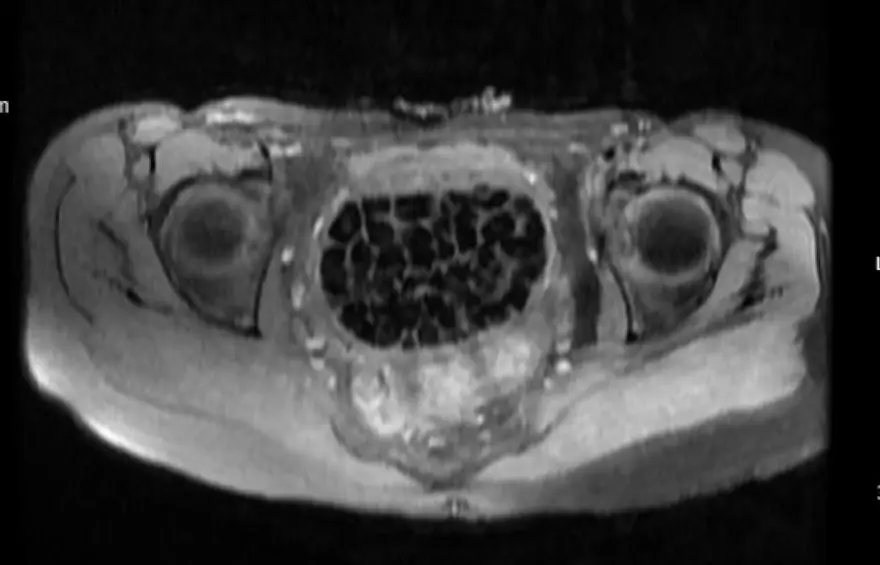

Burada ekipleri tarafından hastanın durumuna ilişkin detaylı incelemeler yapıldı. 2 bölümün iş birliğinde titizlikle yapılan tetkiklerde uzmanlar, vajen isimli noktada taşlar olduğunu tespit etti, Öztürk'ün hemen yatışı yapıldı.

Öztürk’ün vücudundan 287 adet çeşitli ölçülerde taş çıkarılırken üroloji ve jinekolojik onkoloji ekibi operasyonu başarıyla tamamladı. Taşların sayısını duyan genç kız ve ailesi şok olurken operasyonun ardından karın ağrıları dinen Öztürk, rahat bir nefes aldı. Tedavisi sonrası taburcu edilen genç kız yaşadıklarını anlatırken, operasyonu gerçekleştiren doktorlar, genç kızın vücudundaki 287 taşın tetkiklerdeki görüntüsü dikkat çekerken taşlar üzerine de incelemeler yapılacak.

Bir başka uzman da, "Konjental anomali, bunu gebelik esnasında yapmış olduğumuz ultrasongrafi muayenelerinde saptayabiliyoruz. Maksimum 100-110 kadar bir taş vardır diye bir düşüncemiz vardı, sayalım dedik. 287 taş da bizi ameliyat esnasında heyecanlandırmıştı. Saydıktan sonra bu bilgiyi hastamız ve ailesiyle paylaştık. Onlar da şaşkınlık halindeydi, böbrek taşını düşüren bir kişiyle konuştuğunuz zaman bir taşın bile ne kadar zor bir şekilde düştüğünü size tarif edecektir. Taşların uzun yıllar boyunca yavaş yavaş oluştuğunu düşünüyoruz." bilgisini aktardı.